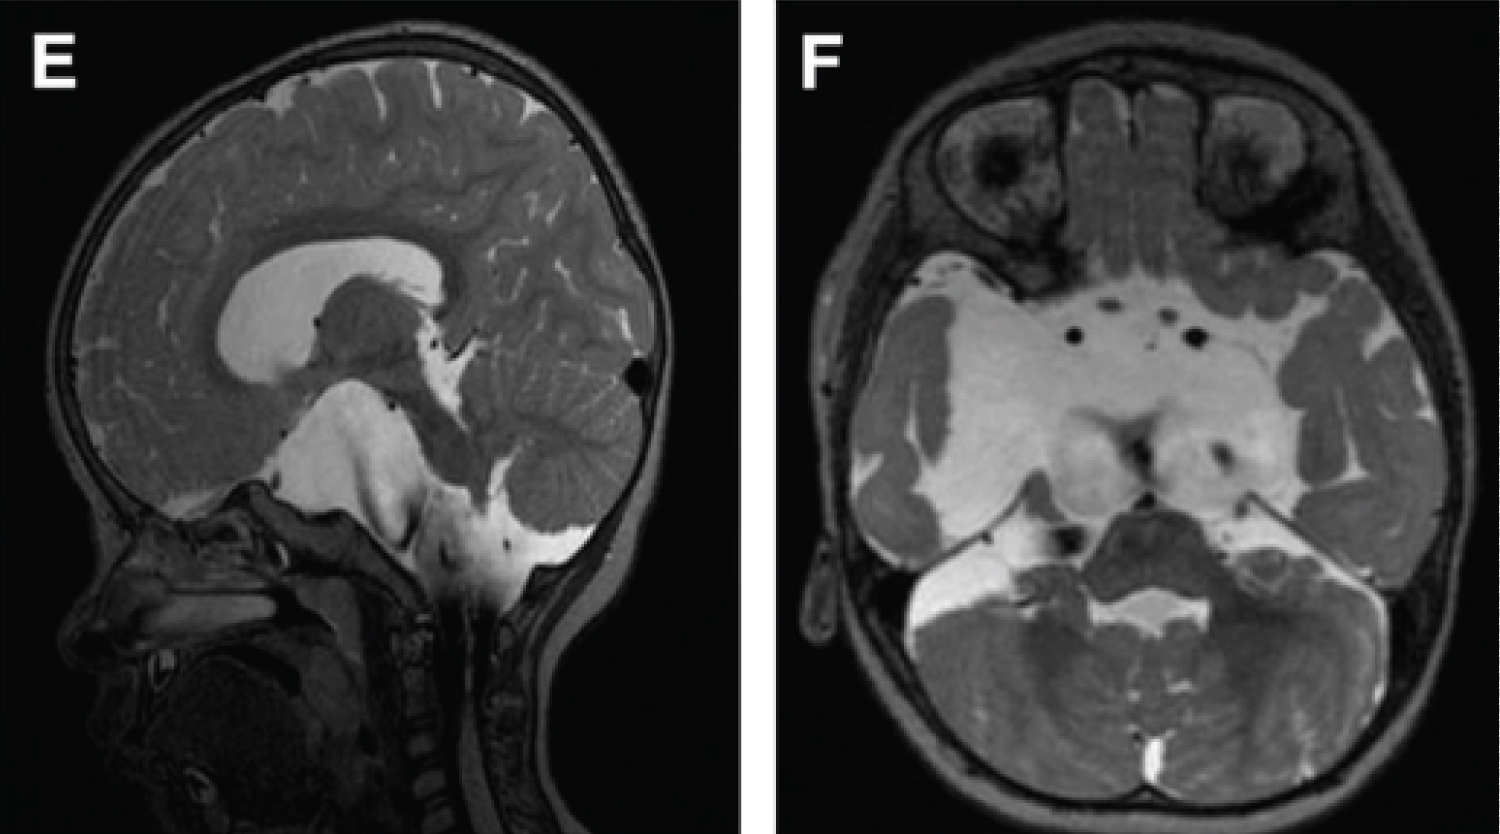

The cyst was rapidly evolutive in the ultrasounds, leading us to conduct a foetal MRI on the 29th week which showed the large cyst, its compression on the brain stem and 4th ventricle, without a ventriculomegaly and no other cerebral anomalies (no sign of parenchymal ischaemia, no morphologic anomalies).

We realized another MRI that showed an asymmetric ventriculomegaly (prevailing on the left side) and a dilatation of the foramen magnum. With this favorable anatomy, we decided to perform a ventriculocystocisternostomy on the 5th day of life.

The MRI after surgery showed a decrease in the size of the ventricles. Unfortunately the ventricles continued to dilate and on the MRI of the 19th day of life, there was a stability in size of the cyst but also a clear tetraventricular hydrocephalus due a residual mass effect on the ambiens cistern and the pons.